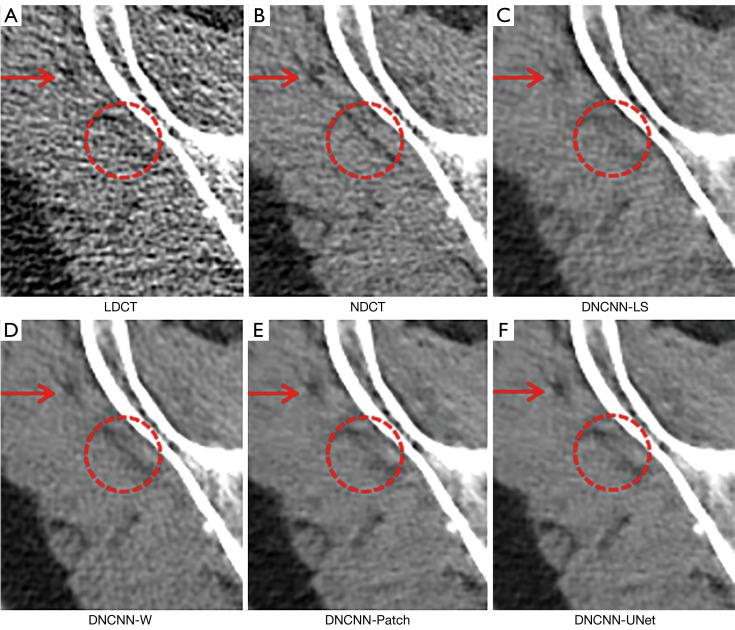

Within the domain of weakly supervised methods, our proposed model exhibited superior objective metrics on the simulated dataset when compared to CycleGAN and selective kernel-based cycle-consistent GAN (SKFCycleGAN): the peak signal-to-noise ratio (PSNR) was 43.9441, the structural similarity index measure (SSIM) was 0.9660, and the visual information fidelity (VIF) was 0.7707. In the clinical dataset, we conducted a visual effect analysis by observing various tissues through different observation windows. Our proposed method achieved a no-reference structural sharpness (NRSS) value of 0.6171, which was closest to that of the NDCT images (NRSS =0.6049), demonstrating its superiority over other denoising techniques in preserving details, maintaining structural integrity, and enhancing edge contrast.

结果

在弱监督方法领域,与CycleGAN和基于选择性内核的循环一致GAN(SKFCycleGAN)相比,我们提出的模型在模拟数据集上表现出更好的客观指标:峰值信噪比(PSNR)为43.9441,结构相似性指数测量(SSIM)为0.9660,视觉信息保真度(VIF)为0.7707。在临床数据集中,我们通过不同观察窗口观察各种组织进行了视觉效果分析。我们提出的方法实现了无参考结构清晰度(NRSS)值为0.6171,最接近NDCT图像的NRSS值(NRSS = 0.6049),表明其在保留细节、保持结构完整性和增强边缘对比度方面优于其他去噪技术。